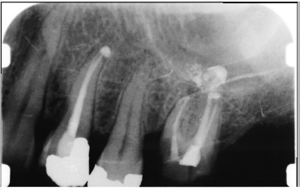

XRAYAt your dental exam/check up our dental hygienist here will:

• use digital radiography for your x-rays